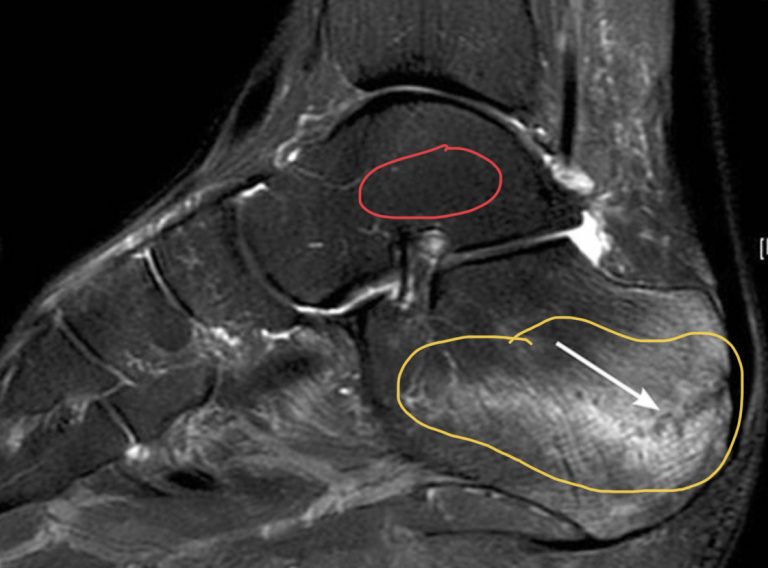

From www.orthofootmd.com

Sprained vs Fractured Ankle What's the Difference? Difference Between Broken Bones When a fracture happens, it’s classified as either open or closed: There are many different types of fractures and as many different treatments methods for each. They mean the same thing. A fracture occurs when a bone is struck by. the main difference between a fractured bone and a bone bruise is that a fracture results in an actual. Difference Between Broken Bones.

From www.vrogue.co

How To Tell The Difference Sprain Verses Fracture Doo vrogue.co Difference Between Broken Bones A broken bone and a fracture are the same; When a fracture happens, it’s classified as either open or closed: In the united states, more than 1 million people a year fracture a bone. The broken ends of the bone line up and are barely out of place. a fracture, commonly known as a broken bone, occurs when a. Difference Between Broken Bones.